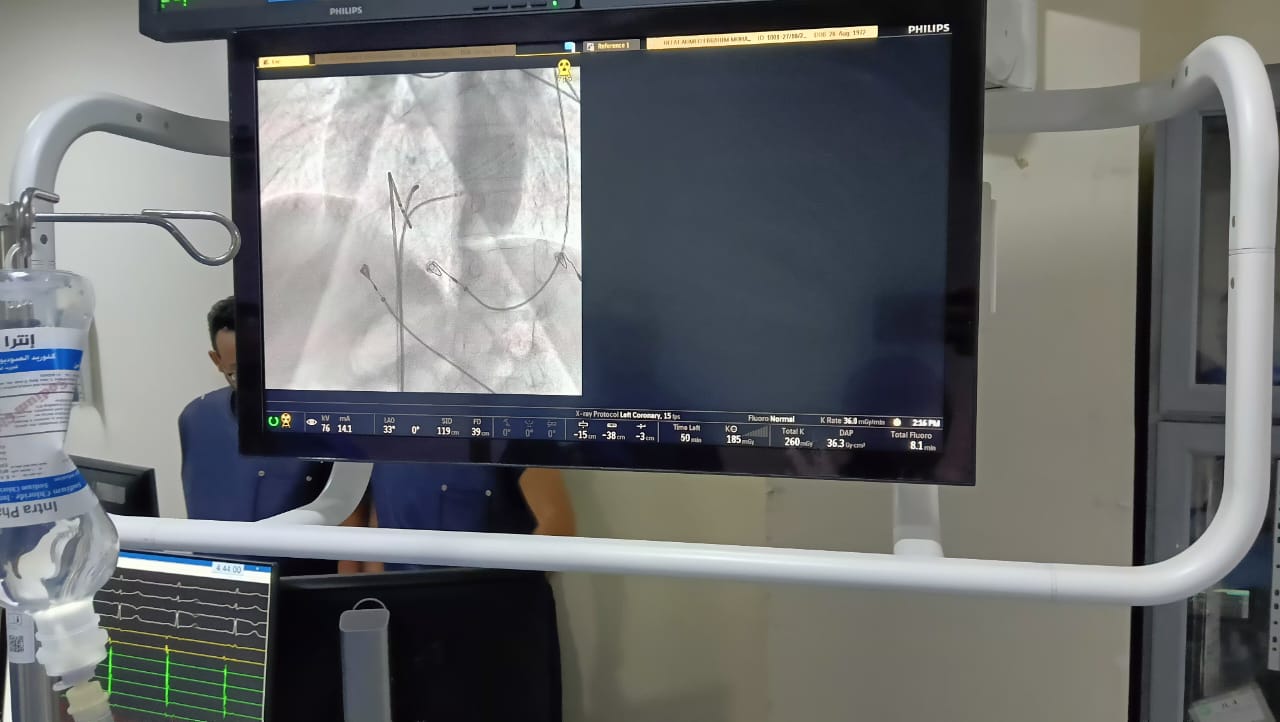

من جانبه أوضح الدكتور حمودة الجزار وكيل وزارة الصحة أنه تم تشغيل جهاز كهربية القلب بمستشفى ميت غمر العام لعلاج اضطراب كهربية وعدم انتظام ضربات القلب بكافة أنواعه من خلال الدراسة الكهروفسيولوجية والكي عن طريق تردد موجات الراديو، وانه يعتبر من أحدث الأجهزة على مستوي العالم تبرعا من المجتمع المدني بقيمة 5.5 مليون جنيه.

وأضاف وكيل وزارة الصحة أنه في أول يوم عمل له في مستشفى ميت غمر استقبلت وحدة القسطرة بالمستشفى مريضا يعاني من خفقان في القلب وتم عمل رسم قلب للمريض وتبين أنه يعاني من تسارع فوق بطيني، وعلى الفور تم دخول الحالة إلى قسطرة القلب وتم عمل قسطرة لدراسة كهروفسيولوجية القلب، وتم خروج المريض بحاله جيده في نفس اليوم.

كما تم في نفس اليوم دخول حالة أخرى لمريض في العقد الخامس من مركز السنبلاوين كان مسجلا بقوائم الانتظار لعمل دراسة كهروفسيولوجية للقلب وتم بالفعل عمل قسطرة قلب وكي البؤرة المسببه لاضطراب ضربات القلب وخرج في نفس اليوم بصحة جيدة.